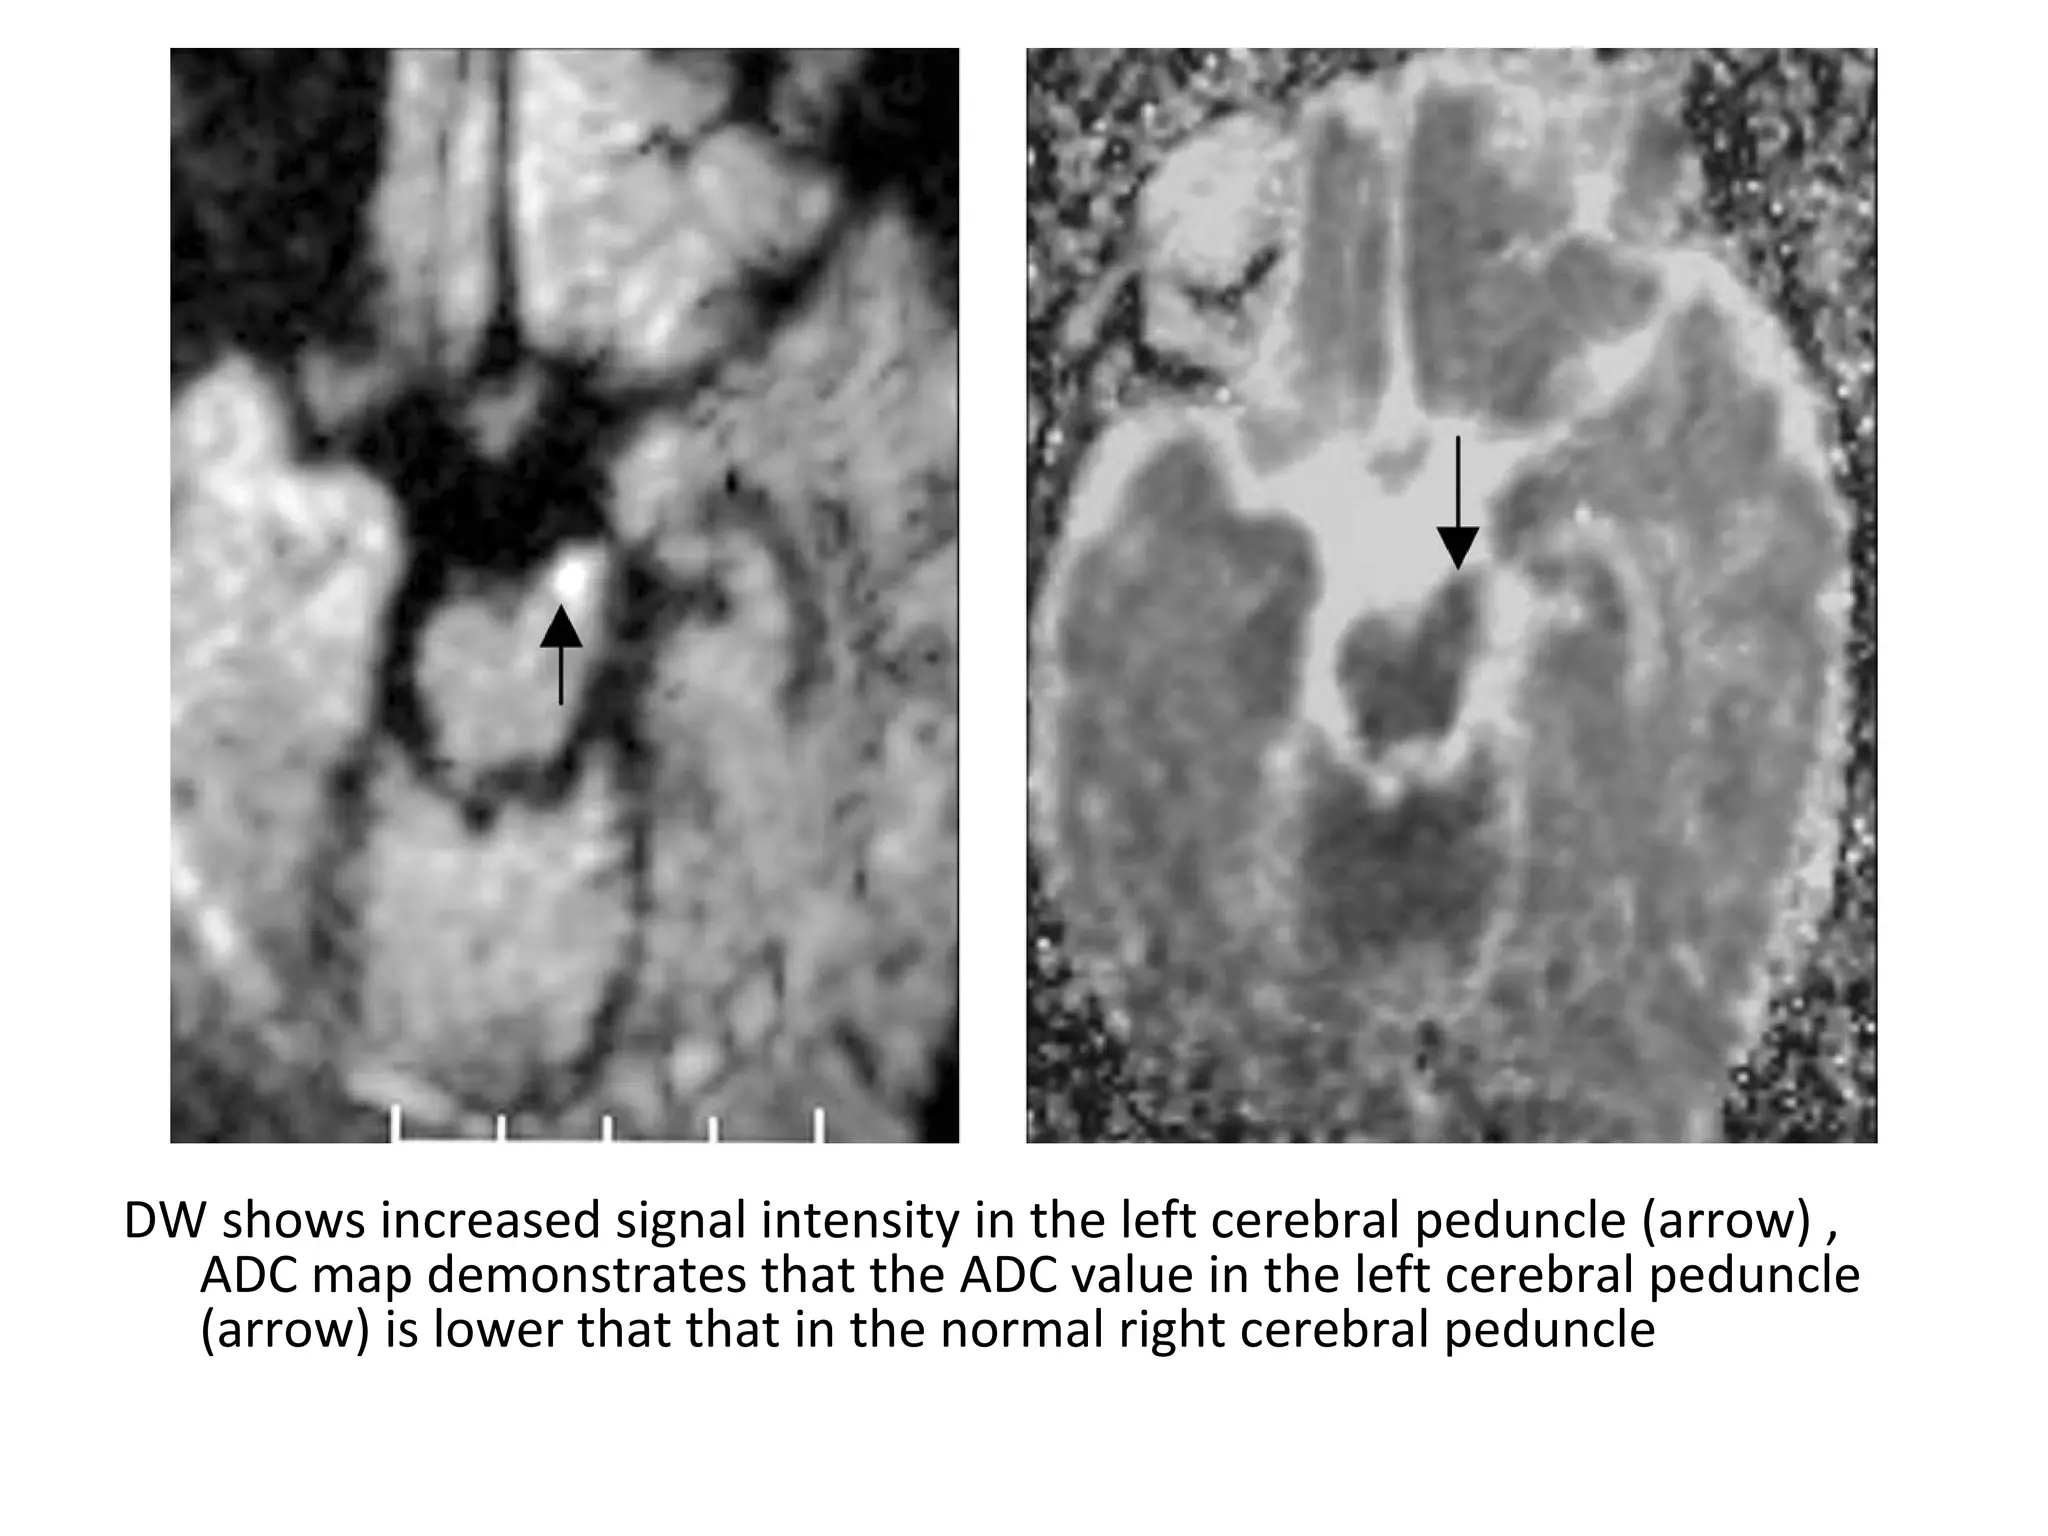

DW shows increased signal intensity in the left cerebral peduncle (arrow) ,

ADC map demonstrates that the ADC value in the left cerebral peduncle

(arrow) is lower that that in the normal right cerebral peduncle